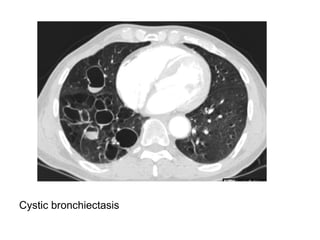

Cystic bronchiectasis